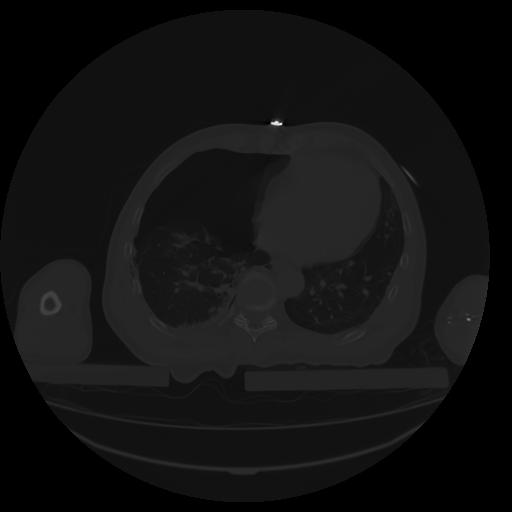

27 CUERPO,CE,Axial,3.0,CUERPO,,